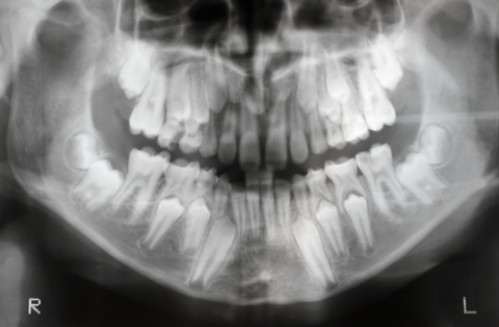

Die dentale Chirurgie umfasst insbesondere Zahnentfernung, die Entfernung retinierter und verlagerter Zähne,  Zahnkeimtransplantationen, Freilegungen retinierter Zähne zur anschließenden kieferorthopädischen Einordnung in den Zahnbogen, Wurzelspitzenabtrennung , Zystenoperationen, die zahnärztliche Traumatologie nach Unfällen und auch die dentale Implantologie sowie die externe Sinusliftoperation.